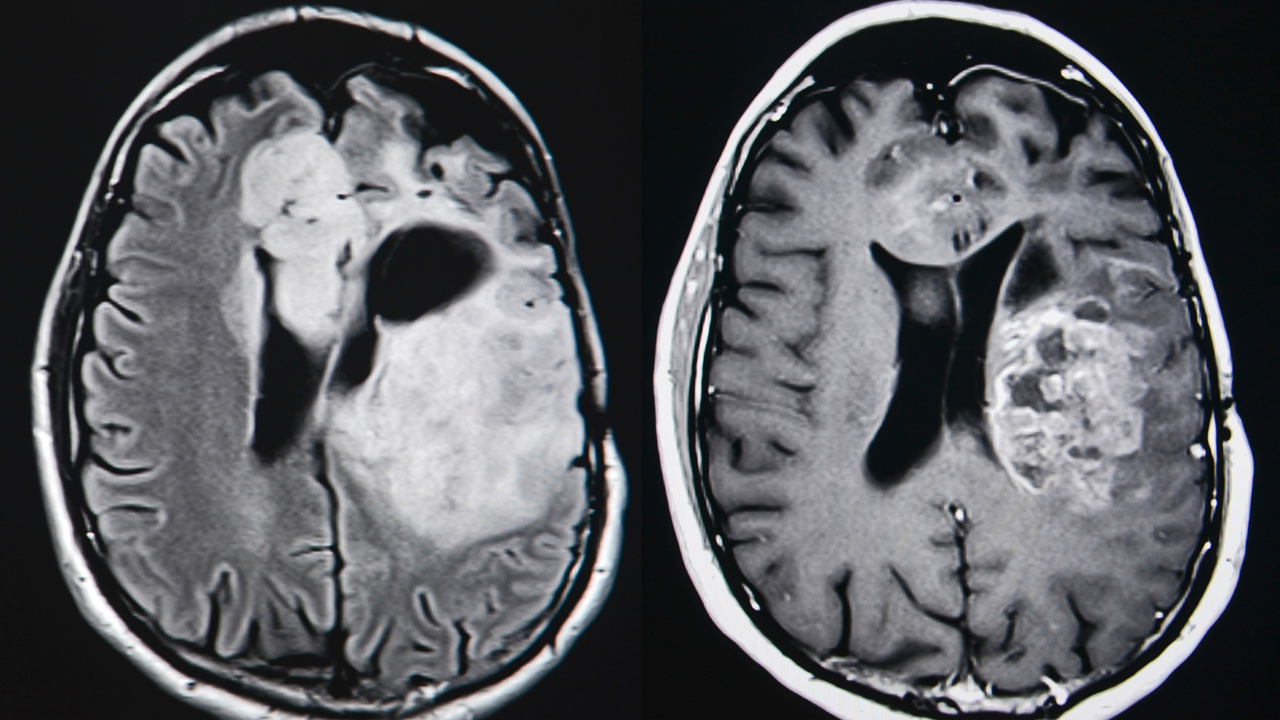

Incurable brain cancer. Glioblastoma is a type of very aggressive brain tumor. Glioblastoma multiforme also known as glioblastoma GBM or grade IV astrocytoma is a fast-growing aggressive type of CNS tumor that forms on the supportive tissue of the brain. See a GP if you have symptoms of a brain tumour that dont go away.

Glioblastoma multiforme GBM the brain cancer that killed Sen. The Brain Tumour Charity is calling on the government to provide free COVID-19 testing for families affected by an incurable brain tumour who are currently travelling abroad for cancer treatment. Life seemed pretty sweet and on track she said.